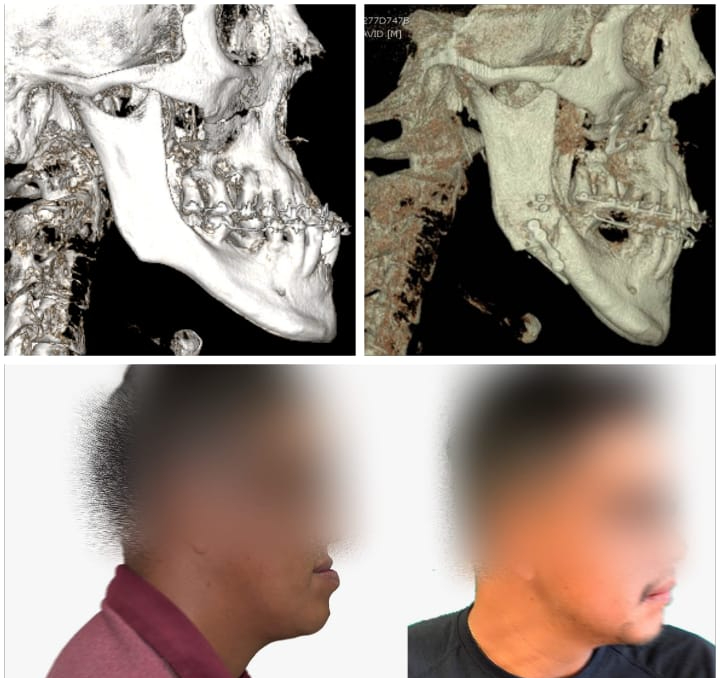

Así mismo la Facultad de Estomatología integra al Servicio de cirugía maxilofacial del Hospital Central “Ignacio Morones Prieto”, nuevas herramientas y tecnologías como los Flujos Digitales para el manejo de pacientes; Se trata de sistemas de alta tecnología como el escáner intraoral y los softwares 3D de última generación, que les permite a los cirujanos anticipar, planificar y simular una cirugía virtual antes de la cirugía real en el quirófano mediante volumetría.

Bajo este sistema los cirujanos logran disminuir los riesgos e imprevistos en el quirófano y se reduce el tiempo de duración de una cirugía y el trauma postoperatorio sobre el paciente. Para solicitar atención de esta especialidad se deberá acudir al servicio de consulta externa del Hospital Central de lunes a viernes en un horario de 8:00 am a 13:00 horas.